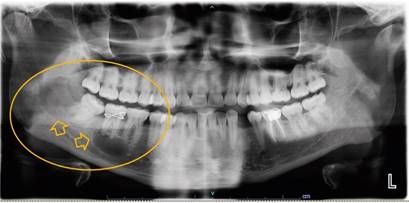

Paciente género masculino, 30 años, derivado desde Centro Atención Primaria de Salud al Hospital San José, por hallazgo radiográfico de lesiones radiolúcidas aparentemente quísticas en rama mandibular derecha y periapice de diente 18 de 1.5 cm de diámetro aprox. en control dental (Fig. 1). No refiere sintomatología. No presenta antecedentes mórbidos ni consumo de fármacos. Niega alergias.

Imágenes por tomografía computarizada se observan 2 lesiones hipodensas aisladas una de la otra ubicadas en cuerpo (Fig. 2) y rama mandibular derecha (Fig. 3), una de ellas comprometiendo periapice de diente 18, ambas lesiones de 1.5 cm de diámetro aproximadamente.